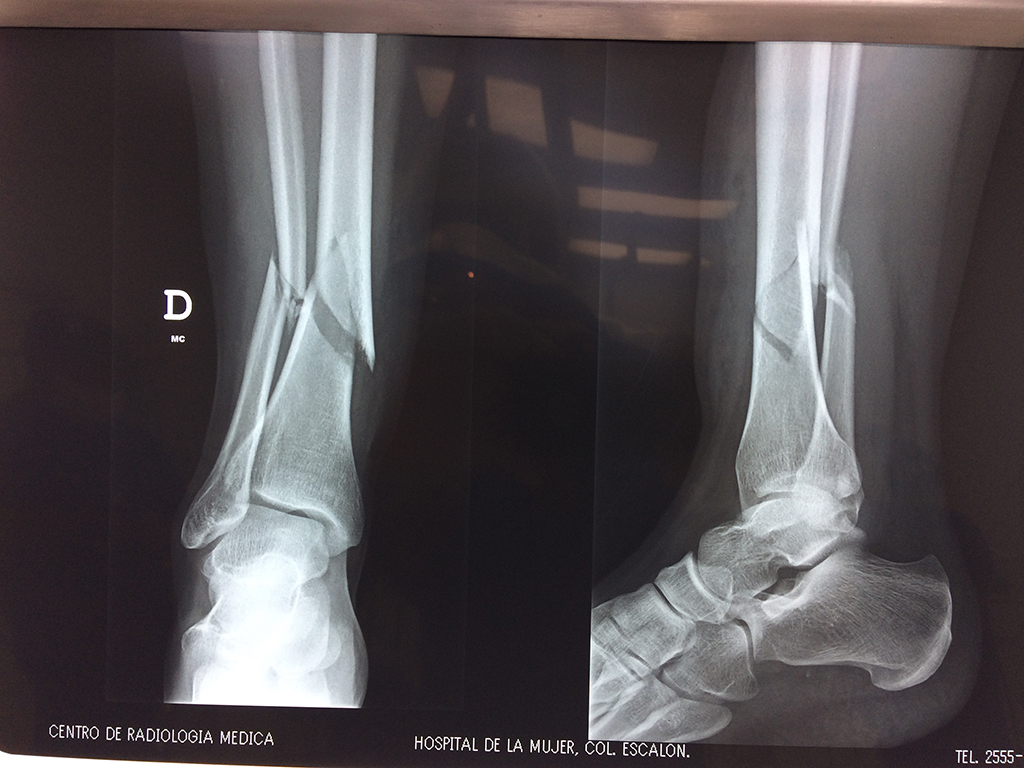

Cirugías de Tobillos

Aunque cada uno de estos huesos puede fracturarse por separado, normalmente la rotura es una lesión que se produce de forma conjunta

La mayor parte de las roturas implican a la parte proximal del hueso (parte del hueso próximo a la rodilla) o a la parte distal (parte del hueso cerca del tobillo).

Debido a la fina cobertura de piel que recubre la tibia y el peroné, las fracturas generalmente son abiertas, es decir, el hueso roto rasga la piel, atravesándola. Las fracturas de tibia y peroné generalmente se producen por un fuerte impacto o torsión.